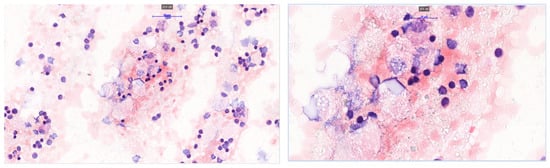

A Rare Case of Multilocular Mesothelial Inclusion Cysts of the Pericardium: Diagnosis, Treatment, Follow Up, with Comprehensive Review of the Literature

by Ali Shadmanian, Kosha Patel, Endre Alács, Henriette Gavallér, Szilva Agocs and Miklós Bitay

Background: Multilocular mesothelial inclusion cysts—also known as benign multicystic mesothelioma (BMM)—are rare, typically arising in the peritoneal cavity. Pericardial involvement is extremely uncommon and can pose diagnostic and therapeutic challenges due to their recurrent and infiltrative nature. Accurate diagnosis and surgical strategy are [...] Read more.

Background: Multilocular mesothelial inclusion cysts—also known as benign multicystic mesothelioma (BMM)—are rare, typically arising in the peritoneal cavity. Pericardial involvement is extremely uncommon and can pose diagnostic and therapeutic challenges due to their recurrent and infiltrative nature. Accurate diagnosis and surgical strategy are critical for management and recurrence prevention. Methods: We present the case of a 36-year-old woman with a prior history of malignant melanoma who developed recurrent multilocular cystic masses of the pericardium. Initial imaging with echocardiography, cardiac magnetic resonance (CMR), and computed tomography (CT) revealed multilocular pericardial cysts. Surgical resection was performed under cardiopulmonary bypass (CPB), but complete excision was limited due to epicardial infiltration. Histopathology confirmed a benign mesothelial origin. One year later, recurrence prompted a second surgical intervention with total pericardiectomy and Gore-Tex patch reconstruction. Results: Postoperative recovery was uneventful in both instances. Follow-up imaging at 6 and 12 months demonstrated no significant recurrence. Histological analysis confirmed benign cysts lined with mesothelial cells, positive for calretinin and WT-1. This represents one of the first documented living cases of pericardial BMM managed with staged surgery and total pericardiectomy. Conclusions: Pericardial BMM is a rare, benign, but potentially recurrent lesion. In cases of extensive or recurrent disease, total pericardiectomy may offer definitive treatment. Multimodal imaging, histopathological evaluation, and personalized surgical planning are essential for effective management. Full article

Show Figures

Figure 1